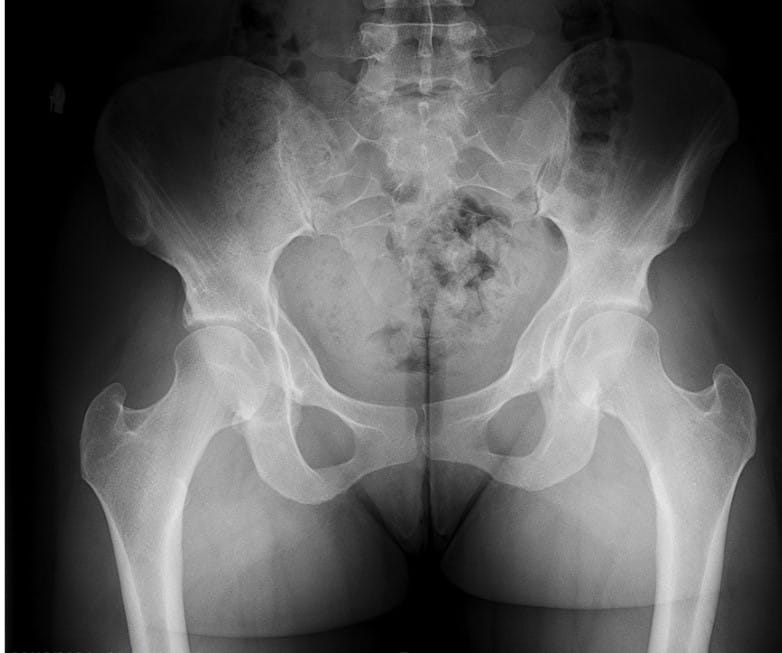

For the past decade, two renowned surgeons at University Hospitals have partnered to advance their novel combined surgical approach to treat concomitant femoral acetabular impingement (FAI) and hip dysplasia.

Dr. Salata performs the first stage of the surgery, using arthroscopic techniques to round the femoral head, improve offset and repair labral damage resulting from FAI. The Director of the Joint Preservation and Cartilage Restoration Center and Division Chief of Sports Medicine at University Hospitals Cleveland Medical Center, he is also a Professor at the School of Medicine and Associate Orthopedic Team Physician for the Cleveland Browns.

Without disrupting the sterile surgical field, Dr. Wetzel next scrubs in and employs an open technique to deepen and reorient the hip socket. “Where University Hospitals differs from other places around the country is that we have been able to maintain a partnership that requires two very vastly different skill sets to execute this surgery to the highest level of efficiency and skill,” he says. “We have the ability to rely on each other as knowledge sources and eliminate single-surgeon bias when we discuss treatment plans with patients.”